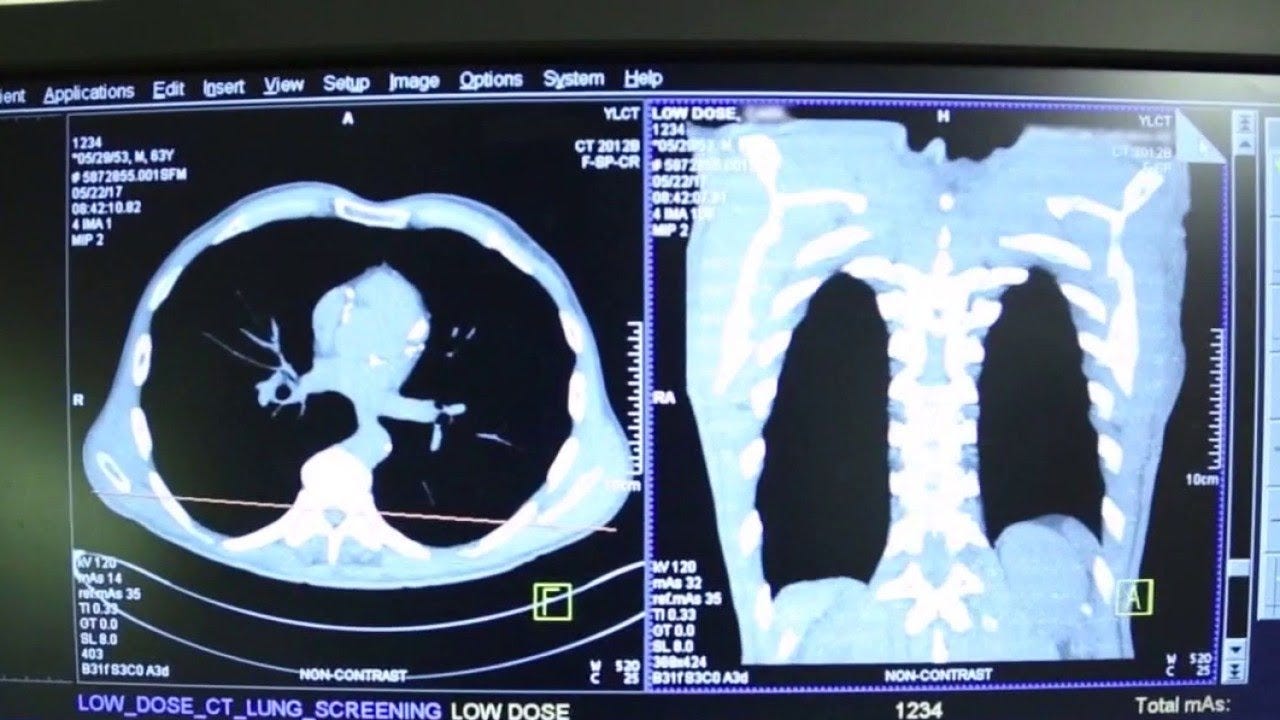

"If you’re eligible, don’t be afraid to get the scan. You can get through this. You’ll be good as new if you can manage to get yourself diagnosed at early stage and so, and that’s what the low-dose lung cancer screening CT is gonna do for you," Butler said.